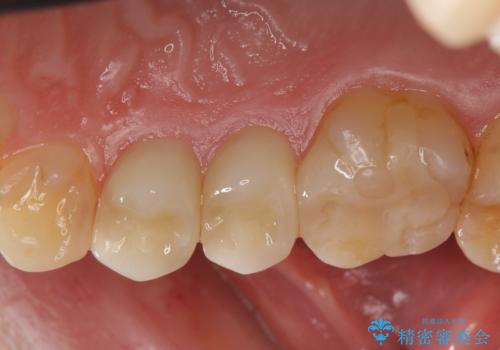

- 右上の銀歯を白くしたいといらっしゃった方の症例です。

右上4、5番目の歯はオールセラミッククラウンによる補綴、6番目の歯はセラミックインレーによる修復を行いました。

今回用いたオールセラミッククラウンは、ジルコニアフレームという白い素材の上にセラミックを盛っているため審美性が非常に高いのが特徴です。

またジルコニアは人工ダイヤモンドの材料にも使われているほど高い強度を持っており、そのためオールセラミッククラウンは審美性だけでなく、奥歯やブリッジの補綴も可能とするクラウンです。

当院のセラミックインレーはemaxという強度と審美性に優れた材料を使用しています。

またプレス方式でインレーを製作しているため、削り出しで製作するCADCAMより優れた適合性も持ち合わせており、虫歯が再発しにくい修復物です。